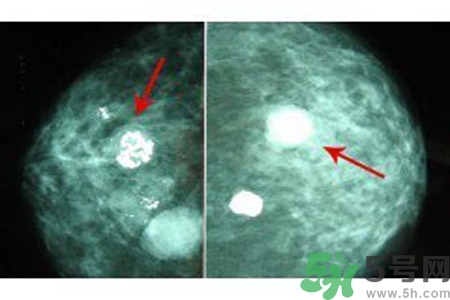

鈣化形態(tài)對辨別病變的良惡性有較大的意義,在觀察中發(fā)現(xiàn)。

顆粒狀、蛋殼狀、不規(guī)則團(tuán)塊狀及軌道狀鈣化多發(fā)生于良性病變。

針尖狀、小桿狀、分叉狀及泥沙樣鈣化多發(fā)生于惡性病變,鈣化的形式多樣、大小差異很大時,惡性的可能性越大,單純出現(xiàn)一種形態(tài)的鈣化時,成簇的針尖狀、分叉狀鈣化,對診斷惡性病變的意義較大。而單純出現(xiàn)泥沙樣鈣化,對病變的良惡性判別則比較困難。泥沙樣鈣化為不確定性鈣化,良惡性有重疊,但如果泥沙樣鈣化伴有其他鈣化形式,提示惡性病變。

乳腺鈣化數(shù)目

良性鈣化一般數(shù)目少,顆粒粗大。惡性病變表現(xiàn)為數(shù)目多,甚至無法計數(shù),如泥沙樣鈣化、成簇的針尖樣鈣化。但有時也可表現(xiàn)為數(shù)量較少,數(shù)顆或數(shù)十顆,數(shù)目少的惡性鈣化常見于分叉狀、小桿狀。1972年Woife提出15~20個/cm2個鈣化點,即可判斷為惡性鈣化。

乳腺鈣化與腫塊的關(guān)系

鈣化可與腫塊并存,也可獨立存在;既可發(fā)生在病變內(nèi),也可獨立于腫塊之外。90%的導(dǎo)管原位癌是通過X線鉬靶照片發(fā)現(xiàn)的,且僅以乳腺內(nèi)鈣化作為惟一的表現(xiàn)形式。這是由于原位癌中央發(fā)生不規(guī)則壞死引起的鈣鹽在導(dǎo)管內(nèi)沉積或腫瘤細(xì)胞分泌而呈形態(tài)各異的的表現(xiàn)。